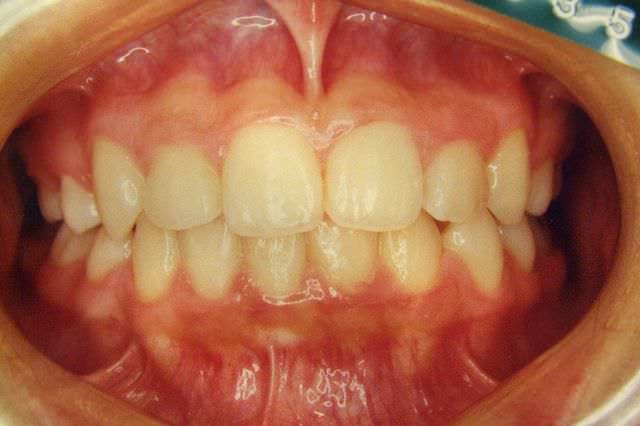

叢生 治療前

治療後

叢生 治療後

主訴 歯並びが気になる

診断名あるいは主な症状 叢生 乱ぐい歯

年齢 13歳0ヶ月

治療に用いた主な装置 ブラケット装置 スタンダードエッジワイズ法

抜歯部位 非抜歯

治療期間 2年5ヶ月

治療費概算 70万+月々の調整料

リスク副作用 歯の根が吸収して短くなる場合があります。

歯茎が痩せて下がる場合があります。

舌で歯を押す唇を噛む等の癖が改善されない場合は、治療期間が長引く場合があります。

定期的に通院できない、キャンセルが多い場合は治療期間が長引きます。